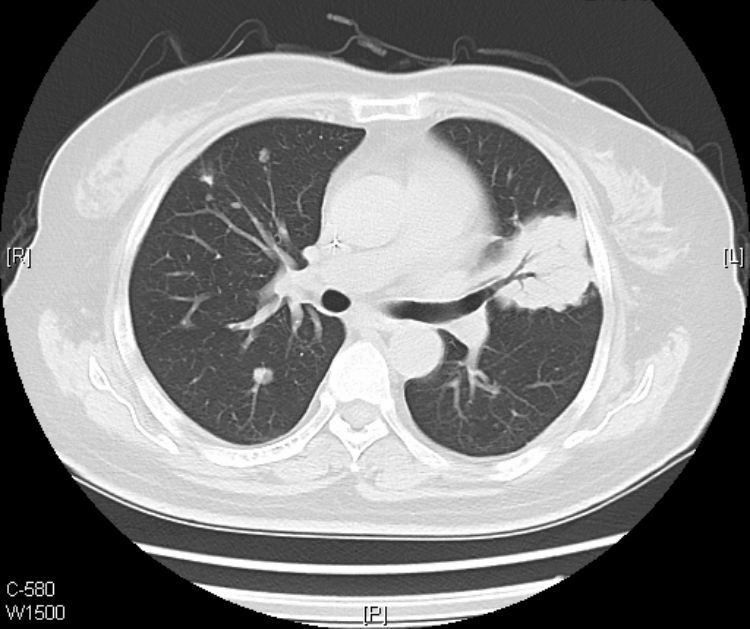

这是一位62岁的小老太,咳嗽咳痰伴低热一个月,伴有白色粘液痰。

胸部平片示重症肺炎表现(2012-7-23),临床伴有II型呼吸衰竭表现。

在影像上,黏液腺癌分两种类型:结节肿块型和肺炎型。

肺炎型的初期常被误诊为肺炎,上图的老太太就属于这个类型。

接着看她往下的CT层面:

从CT片上我们可以看到:老人的黏液腺癌还发生了气道转移。

CT提示气道播散的征象包括:多发小叶中心结节,分支模糊呈树芽征,通常边界不清,可见磨玻璃影。